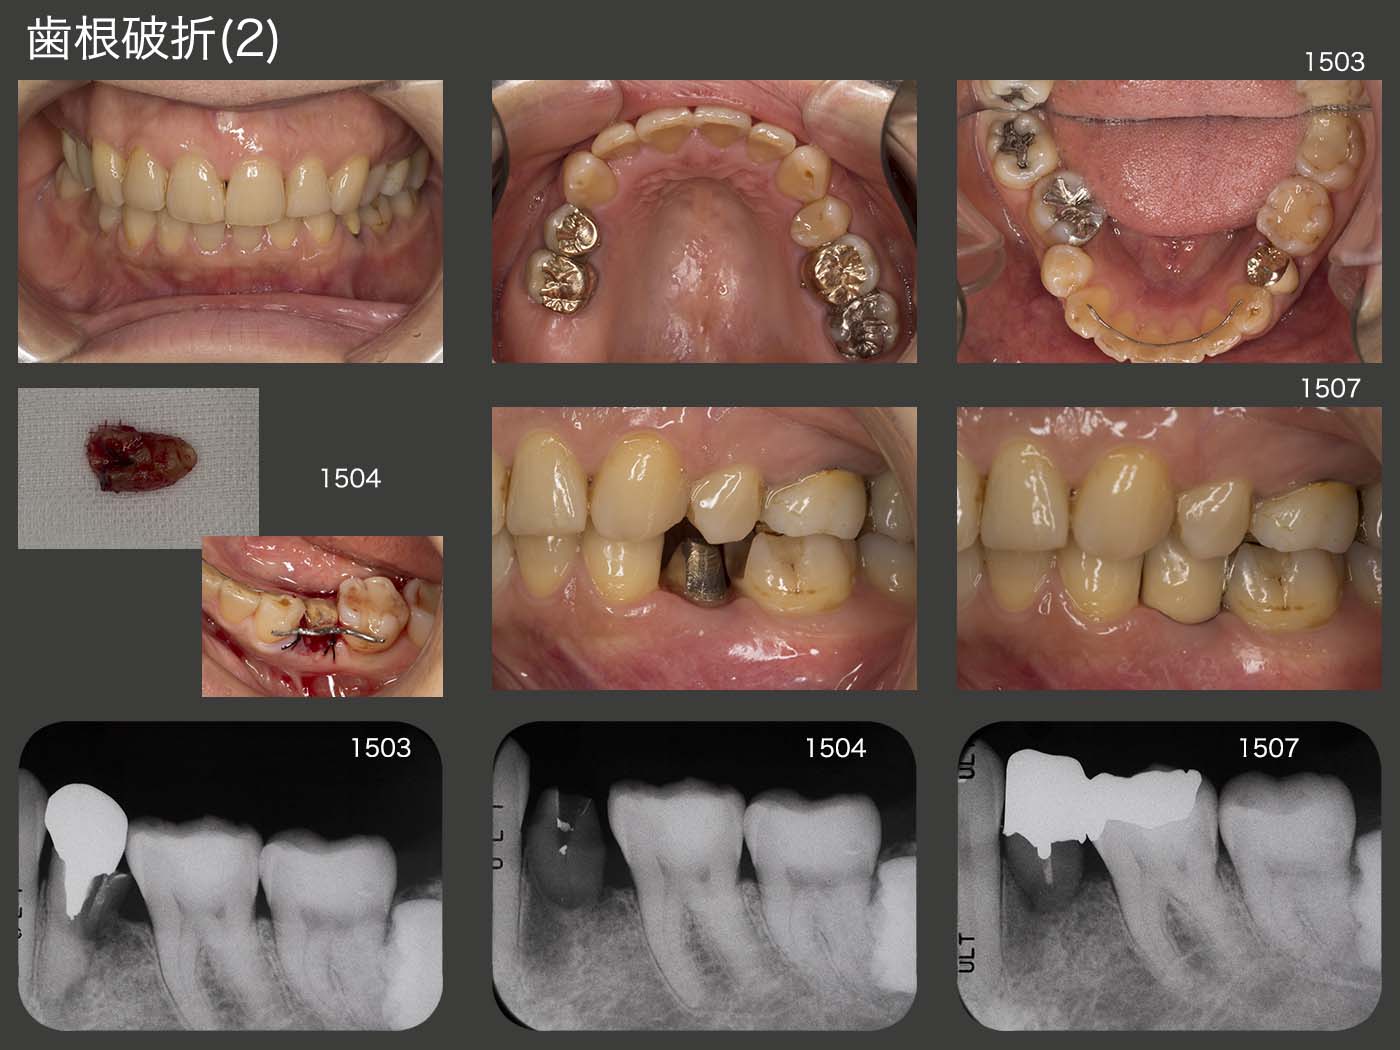

2015年3月初診、55歳の女性。左下4の咬合時痛を訴えて来院。デンタルX線写真から歯根破折がみられた。右側は、右上7が欠損で右下6が舌側に転位しているため、右側では咬みにくく、どうしても左側咬みになってしまう。この結果、無髄歯である左下4の歯根破折が生じたものと考えられる。

破折は根尖側から3分の1にまで達していたが、何とか保存したいと考えて再植を行った。さすがに単独植立は無理なので、左下6のコンポジットレジンを除去し、左下5および6の連結冠を装着した。ブリッジであれば、バージントゥースである左下3を削る必要が生じるが、再植によって回避することができた。